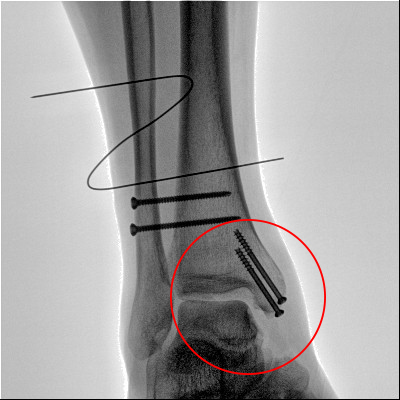

踝关节骨折在X影像上的表现有很多种。如内踝骨折和外踝骨折,我们可以在影像上看到骨折处的骨折线是不连续的?;褂泻篚椎墓钦郏邗?、外踝、后踝联合在一起发生的骨折,我们称之为“三踝骨折”,这些都是在X影像上能够显示出来的。

内踝骨折

外踝骨折

后踝骨折

三踝骨折